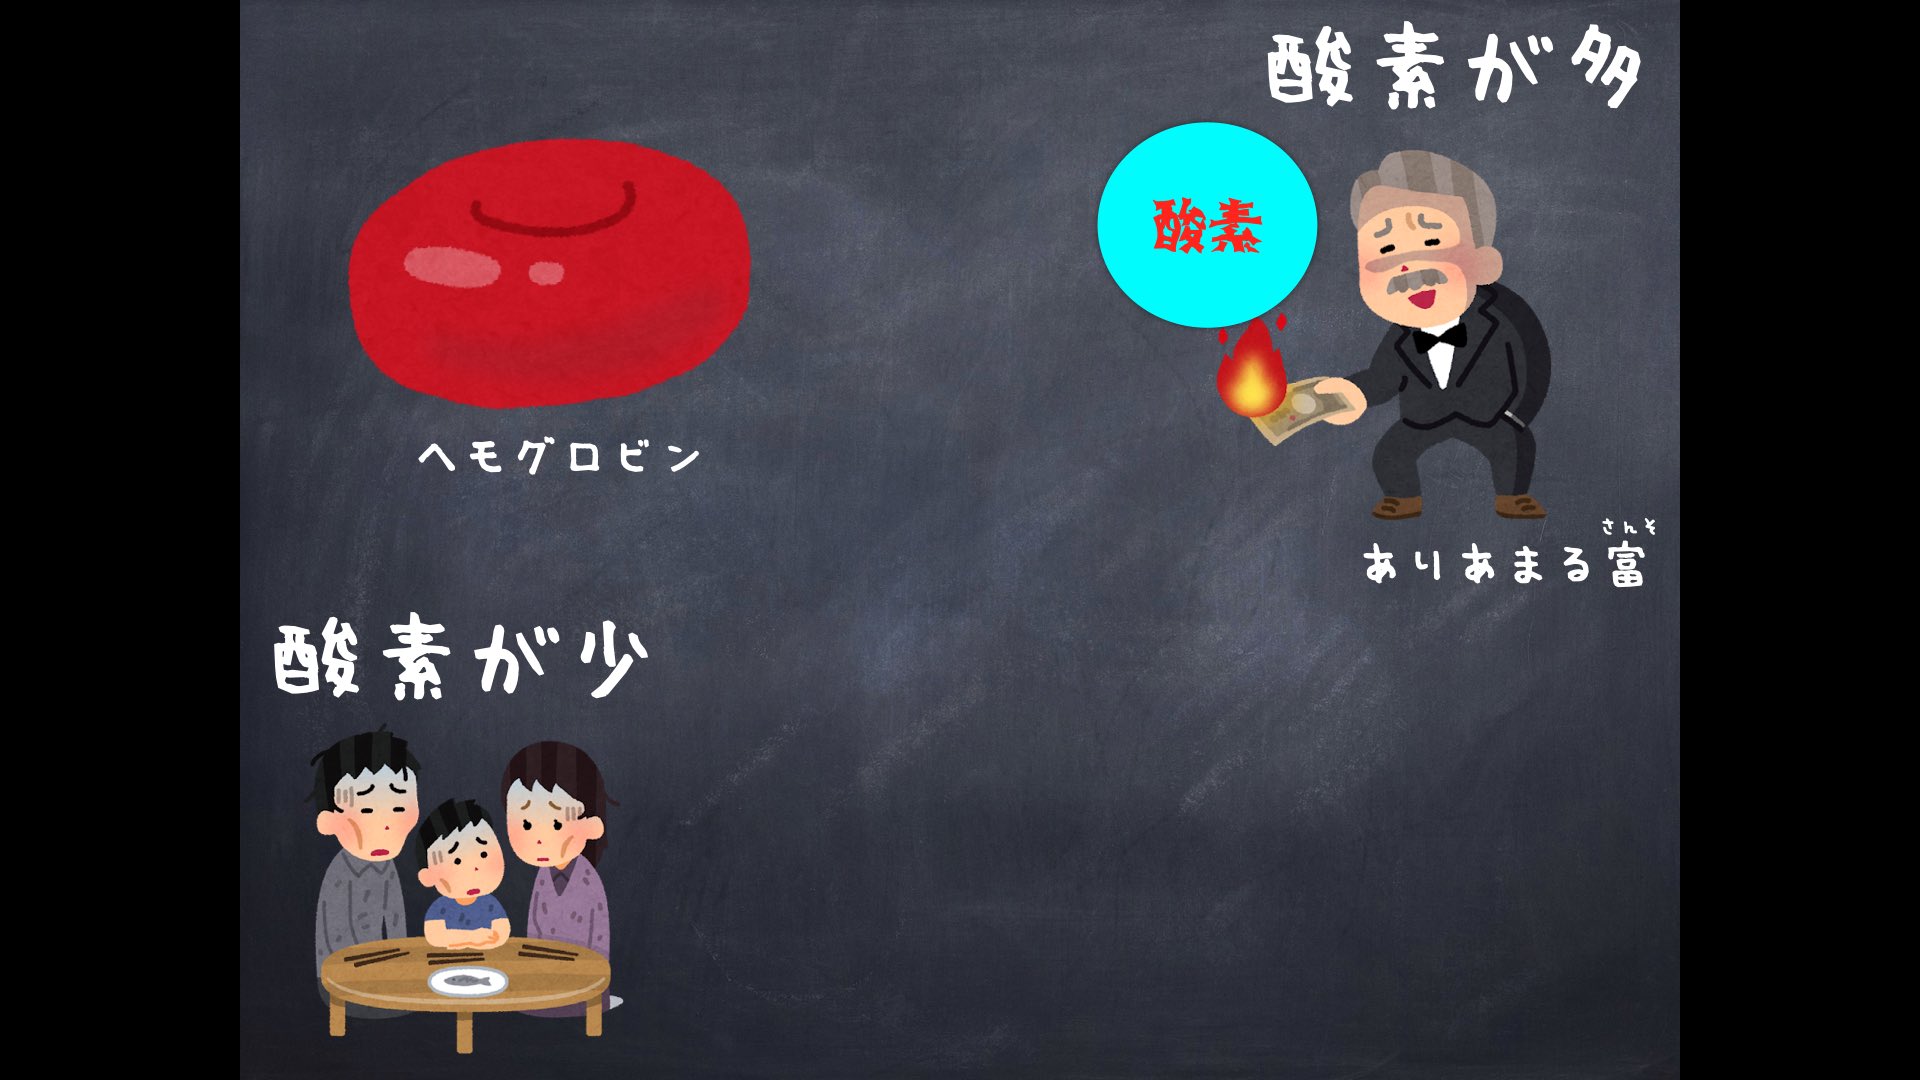

Uzivatel マーミレー先生 Na Twitteru 今回はいらすとやさんのイラストをお借りしてつくっています いらすとや さん やっぱり凄いですね 赤血球のイラストも肺のイラストもありました

تويتر マーミレー先生 على تويتر 今回はいらすとやさんのイラストをお借りしてつくっています いらすとや さん やっぱり凄いですね 赤血球のイラストも肺のイラストもありました T Co Oo3edl6zrr